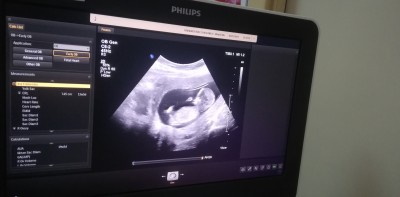

13 haftalık görüntüsü cinsiyetini çok merak ediyorum

Gebelik haftası 18

Yok canım tahmin vermedi 5 dk bakip gönderiyorlar zaten  resimde 13 hftaliktim şuan 18 haftamdayim

Ufak bir çıkıntı var erkek gibi geldi bana sağlıkla kucağına alırsın inşallah canım